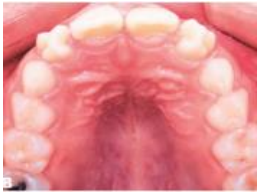

Observe a imagem, abaixo:

Ao analisarmos a imagem, o que se observa, que justifique a maloclusão, é a presença de cúspide em: